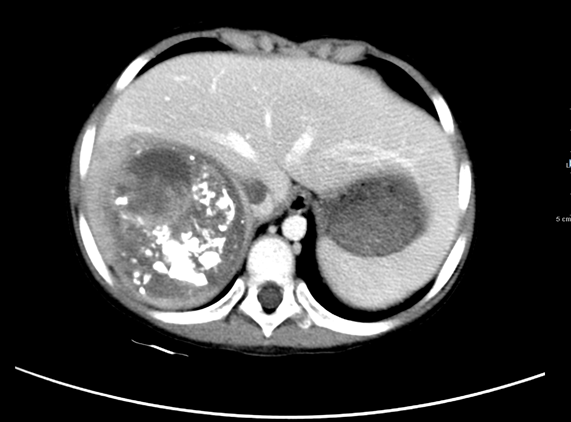

2011年1月19日于中山一院行“右半肝切除+下腔静脉瘤栓去除术”。

术后病理示:肝母细胞瘤。

图4 手术后CT